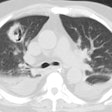

CXR demonstrates migratory infiltrates, but after 1 to 2 months the lesions become stable nodules or cysts predominantly in the lower lobes. Pleural effusions can be seen.CT findings include poorly marginated peripheral or subpleural nodules measuring approximately 2cm (up to 74% of cases) with surrounding ground-glass and a streaky opacity connecting the nodule to the pleural surface [3], pleural effusion, hydropneumothorax, airspace consolidation, and thin walled cysts [1,2].